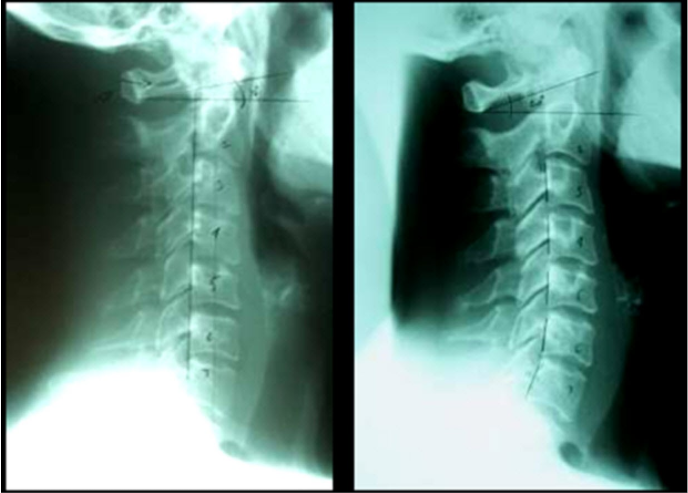

X-rays

If you plan on making a change to a person’s spine, then radiographs are a great way to demonstrate those changes. Again, a picture is worth a thousand words. So show them how their spine is not normal. And over time, show them how it improves. I loved showing my patients before and after x-rays of other patients in my report of findings.

It would go something like this. “Mary, let me show you some examples of people similar to you who I helped. Here’s a patient with a straight neck. You can see their neck is very straight and the C1 angle is only 10 degrees. Again, the normal shows this vertical line falls inside the seventh cervical and the C1 angle is normally 25 to 35 degrees. Here is their follow-up film X-months later. Look at the great results she got. We restored her cervical curve and all her complaints were resolved.”

Same as with the posture pics, I would recommend you give your patients copies of their x-rays. Back in the day before digital x-rays, I would just use their flip phone to take some pics of their films on the view box. Did I just age myself ;-).

Nowadays with digital x-ray, you can email them a copy with your line drawing and notes written right on them. Make it easy for them to share with family and friends. Again, everyone’s favorite subject is them-self. I would routinely get referrals exactly this way.